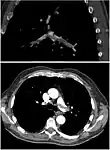

Ventilation/perfusion scan

Ventilation-perfusion scintigraphy

(A) After inhalation of 20 mCi of Xenon-133 gas, scintigraphic images were obtained in the posterior projection, showing uniform ventilation to lungs.

(B) After intravenous injection of 4 mCi of Technetium-99m-labeled albumin, scintigraphic images shown here in the posterior projection. This and other views showed decreased activity in multiple regions.

A ventilation/perfusion scan (or V/Q scan or lung scintigraphy) shows that some areas of the lung are being ventilated but not perfused with blood (due to obstruction by a clot).[18] This type of examination is as accurate as multislice CT, but is less used, due to the greater availability of CT technology. It is particularly useful in people who have an allergy to iodinated contrast, impaired kidney function, or are pregnant (due to its lower radiation exposure as compared to CT).[63][64][65] The test can be performed with planar two-dimensional imaging, or single photon emission computed tomography (SPECT) which enables three-dimensional imaging.[56] Hybrid devices combining SPECT and CT (SPECT/CT) further enable anatomic characterization of any abnormality.[66]